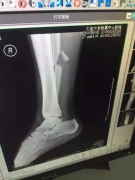

Улан Конысбаев сможет ходить только через три месяца, - врачи Полузащитник сборной Казахстана по футболу Улан Конысбаев, получивший перелом, неудачно приземлившись на ногу во время матча с Китаем, сможет ходить только через три месяца. Таке прогнозы делают китайские медики, передает newtimes.kz.

"Улан Конысбаев получил перелом в концовке первого тайма. Футболиста с поля увезли в больницу. В результате перелома у него порваны боковые связки, плюс связки между малой и берцовой костью. Операция длилась 3,5 часа.Улан Конысбаев сможет ходить только через три месяца, - врачиПо словам врачей, все прошло нормально. Отмечается, что Улан Конысбаев сможет ходить только через три месяца. При этом некоторые шурупы в ноге уберут почти через год", - говорится в публикации.